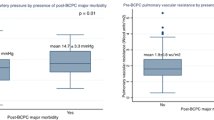

After BCPA, PBF is derived only from the upper body venous return, which, in the infant, largely reflects cerebral blood flow (CBF). Under these circumstances, the cerebral and pulmonary auto-regulatory mechanisms are in direct competition with each other, and the net result on organ perfusion will be different from that in individuals with normal ventricle physiology [2–4]. A unique consequence of BCPA [2, 3] circulation is that systemic arterial oxygenation is the weighted average of deoxygenated blood coming from the inferior vena cava and oxygenated blood from the pulmonary veins. CBF and its auto-regulation may have important clinical implications for the postoperative management and early and late neurodevelopmental outcomes after BCPA [5–8]. Hypercapnia with acidosis increases CBF [9–12] and reduces PBF by increasing pulmonary vascular resistance (PVR) in normal circulation, after cardiopulmonary bypass (CPB), and during anesthesia [13–15]. A unique aspect of PBF physiology after BCPA is the interaction of two highly autonomically regulated vascular beds—cerebral and pulmonary circulation—that have opposite responses to changes in CO2 and acid–base status.

Comparing the breathing patterns and resulting ventilator pressures at similar assist levels during PSV and NAVA, respectively, there were no differences between PSVlow and NAVAlow, whereas there were differences between PSVhigh and NAVAhigh. V T, PIP, and MAP were significantly higher during PSVhigh than during NAVAhigh (Table 3). Comparing the arterial blood gases between the two modes (NAVA and PSV) at the same level of assist, SaO2 (81.9 ± 8.6 vs. 79.6 ± 10.3 %; P < 0.01) was higher and PaCO2 (37.6 ± 6.4 vs. 39.9 ± 6.8 mmHg; P < 0.01) was lower during NAVAlow than during PSVlow. At the higher level of assist, a lower pH (7.42 ± 0.03 vs. 7.45 ± 0.06; P < 0.01), a higher PaCO2 (38.1 ± 6.0 vs. 34.5 ± 6.6 mmHg; P < 0.01), and a higher SaO2 (82.0 ± 7.5 vs. 79.0 ± 9.1 %; P < 0.01) were observed during NAVAhigh compared to PSVhigh. The PI of MCABF was lower in NAVA than in PSV at both assist levels [1.1 ± 0.3 vs. 1.2 ± 0.3 at the lower assist level (P < 0.01) and 1.2 ± 0.3 vs. 1.3 ± 0.4 at the high assist level (P < 0.01)]. V d, but not V s or V m, of MCABF (35.2 ± 13.1 vs. 34.7 ± 12.8 m/s; P < 0.01) was higher during NAVAhigh than during PSVhigh.

The determinants of systemic oxygenation after the BCPA are multifactorial and depend upon PBF, CBF, cardiac output, and intrapulmonary shunting [20–22]. A unique aspect of the physiology of PBF after BCPA is the interaction of two highly autonomically regulated vascular beds—the cerebral and the pulmonary circulation—that have opposite responses to changes in CO2 and acid–base status [23–25]. It has been reported that hyperventilation to achieve lower PVR impairs oxygenation, while hypoventilation improves oxygenation in patients after BCPA [12, 14, 15, 20, 21]. Li et al. [12] reported that moderate hypercapnia with respiratory acidosis improved arterial oxygenation and reduced oxygen consumption and arterial lactate levels, thus improving overall oxygen transport in children after BCPA. Fogel et al. [13] reported that PaCO2 had a major influence on CBF and PBF distribution, whereas changes in PO2 had only a minor impact. They concluded that increased CO2 tension in patients after BCPA results in increased blood flow to the brain and lungs, improved PaO2, increased cerebral O2 transport, and increased cardiac index, which accounted for the increased CBF. Hoskote et al. [14] demonstrated that increasing PaCO2 from 35 to 55 mmHg improved systemic oxygenation, systemic blood flow, CBF, and PBF. It also decreased systemic vascular resistance without increasing PVR after BCPA. The improvement in oxygenation with hypercapnic acidosis suggests that an increase in cerebral and systemic blood flow overrides the vasoconstrictive effect of hypercapnic acidosis on PVR after BCPA [12–14, 20, 21]. In the first period of our study, we confirmed that hyperventilation due to an excessively high V T did not improve the systemic oxygenation in BCPA circulation; instead, it tended to accentuate hypoxemia. PVR, which depends on the balance in the vascular tone of its two components: the alveolar vessels and the extra-alveolar or parenchymal vessels, is directly affected by changes in lung volume. When the lung is inflated above functional residual capacity, PVR is elevated because the alveolar vessels become compressed as a result of alveolar distension. Meanwhile, the blood flow from the SVC returning to the lung is reduced because of the elevated intrathoracic pressure as a result of high ventilation pressure. These help to explain the effect of lower saturation when the patients after BCPA were hyperventilated, although the cardiovascular effects of mechanical ventilation are complex. The decrease in MCA flow velocity is a major issue as it decreased PBF and the delivery of oxygenated blood into the systemic circulation.